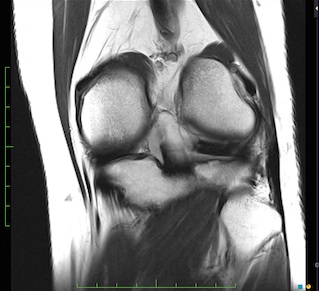

Figure 3 for case Meniscal ossicle

Figure 3